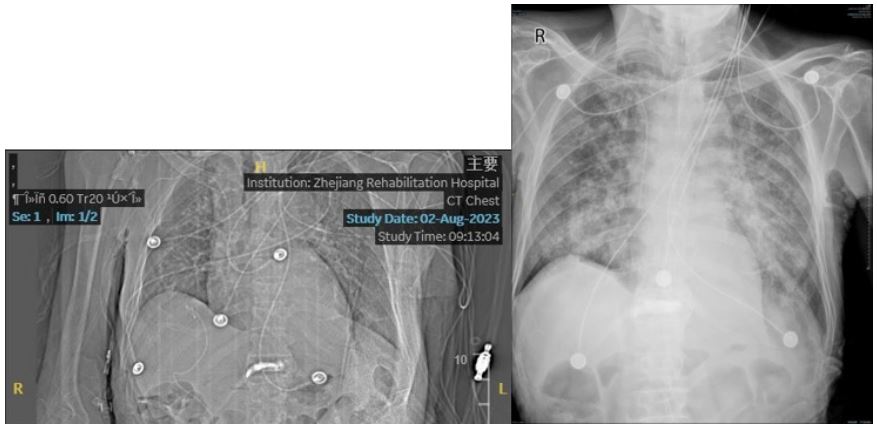

Figure 4: His bedside X-ray results before and after.